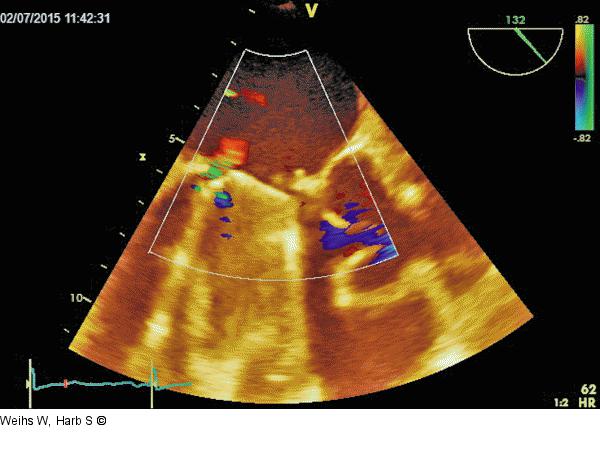

Abbildung 2: Mitralklappenprothese - Regurgitation Paravalvuläres Leak mit geringfügiger Regurgitation. |

Paravalvuläres Leak mit geringfügiger Regurgitation. |